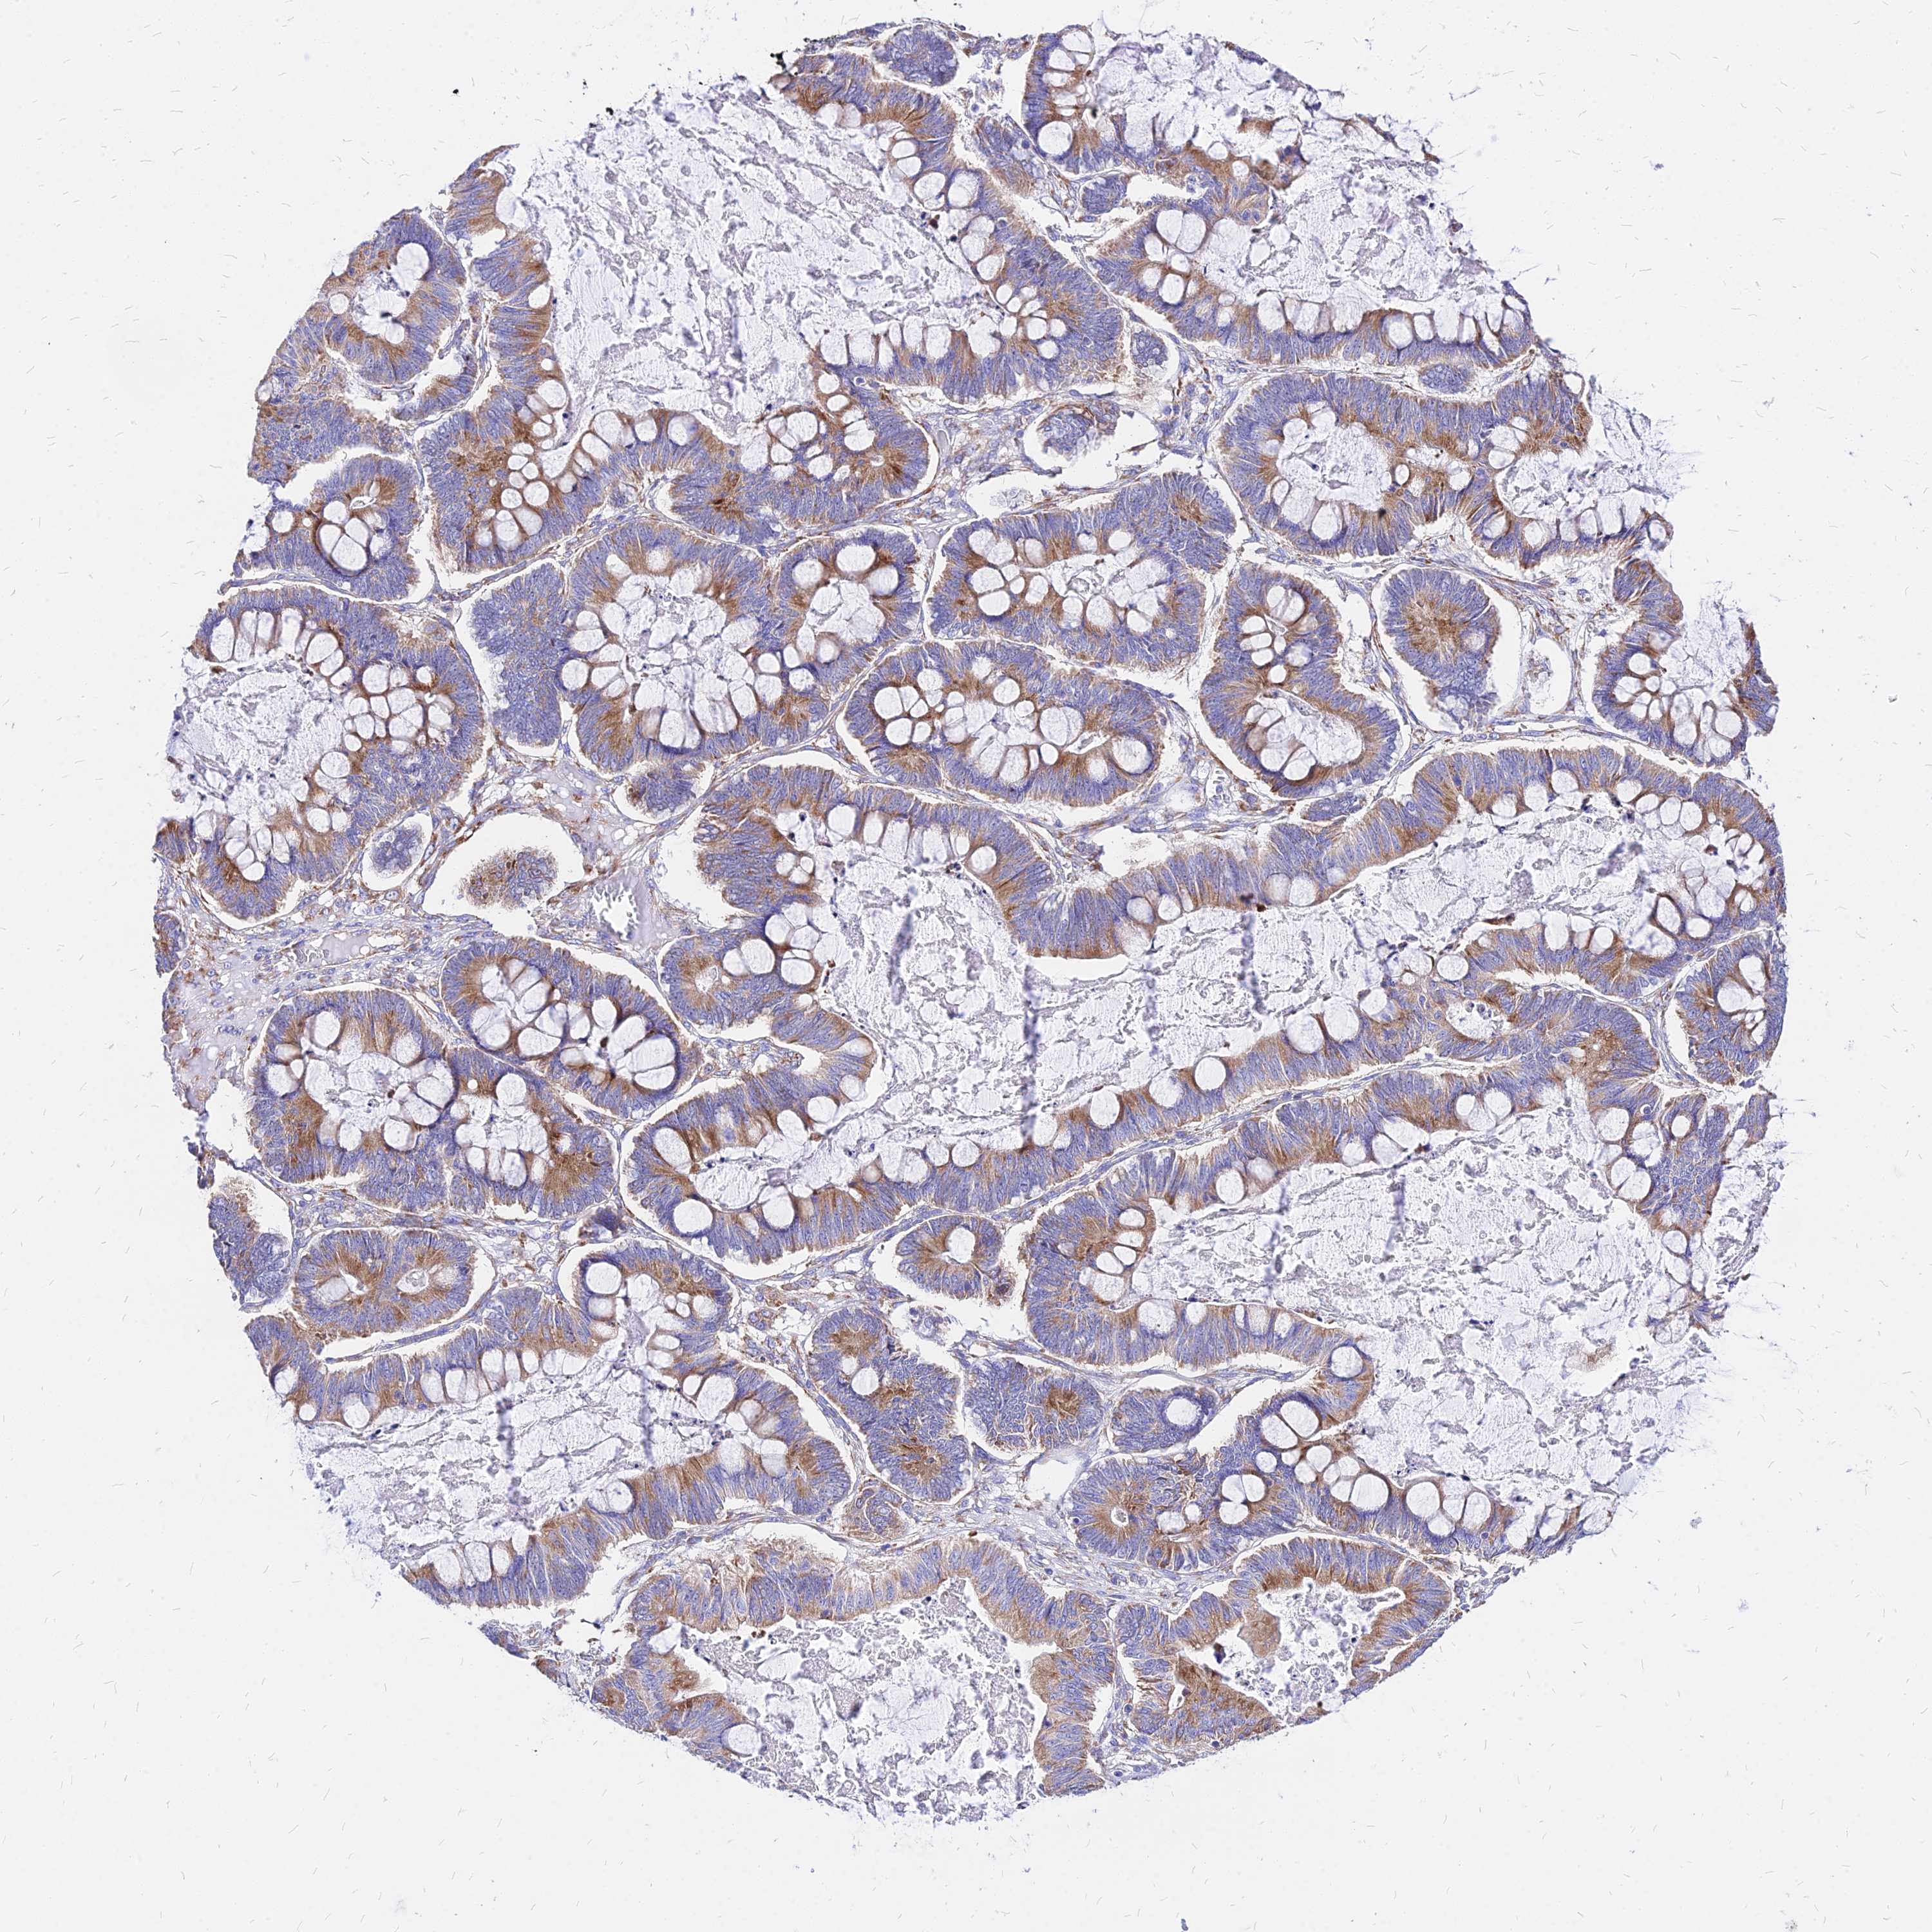

OVARIAN CANCER - Protein expressioni

A mouse-over function shows sample information and annotation data. Click on an image to view it in a full screen mode. Samples can be filtered based on level of antibody staining by selecting one or several of the following categories: high, medium, low and not detected. The assay and annotation is described here.

Note that samples used for immunohistochemistry by the Human Protein Atlas do not correspond to samples in the TCGA dataset.

Antibody stainingi

Antibody staining in the annotated cell types in the current human tissue is reported as not detected, low, medium, or high, based on conventional immunohistochemistry profiling in selected tissues. This score is based on the combination of the staining intensity and fraction of stained cells.

Each image is clickable and will lead to virtual microscopy that enables deeper exploration of all samples and also displays staining intensity scores, fraction scores and subcellular localization as well as patient and tissue information for each sample.

Antibody HPA043014

Staining

High

Medium

Low

Not detected

Intensity

Strong

Moderate

Weak

Negative

Quantity

>75%

75%-25%

<25%

None

Location

Nuclear

Cytoplasmic/membranous

Cytoplasmic/membranous,nuclear

Cystadenocarcinoma, serous, NOS

Carcinoma, NOS

Cystadenocarcinoma, mucinous, NOS

Carcinoma, endometroid